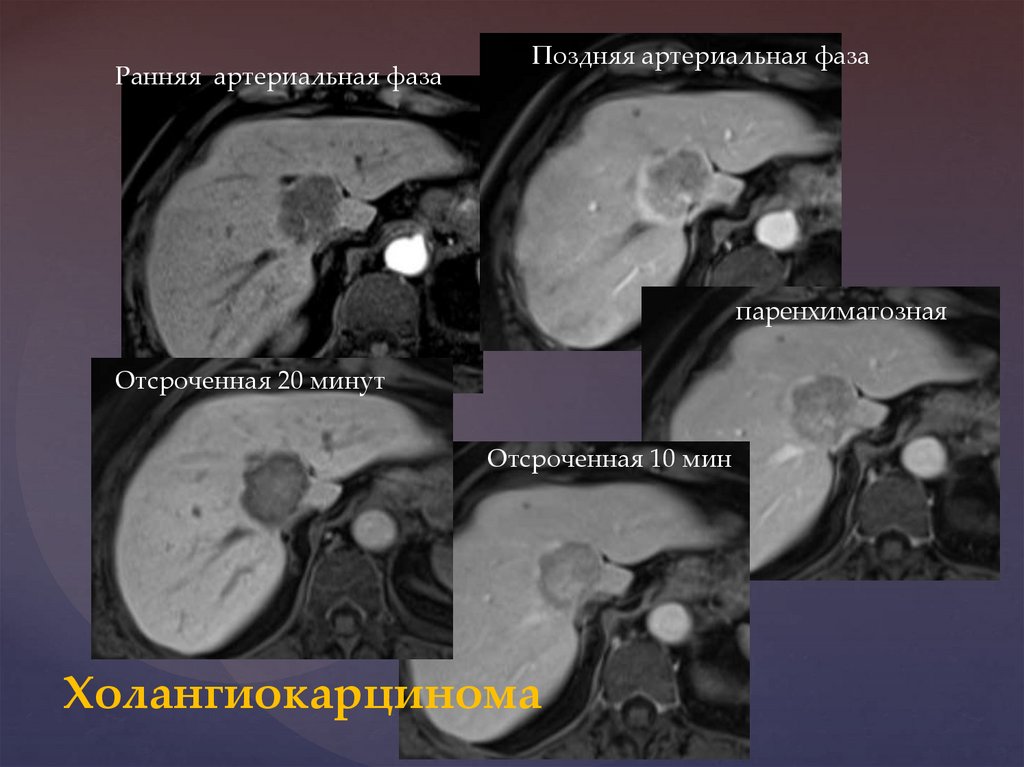

Методы динамического контрастирования печени на МРТ

Раздел: Снимки-подсказки